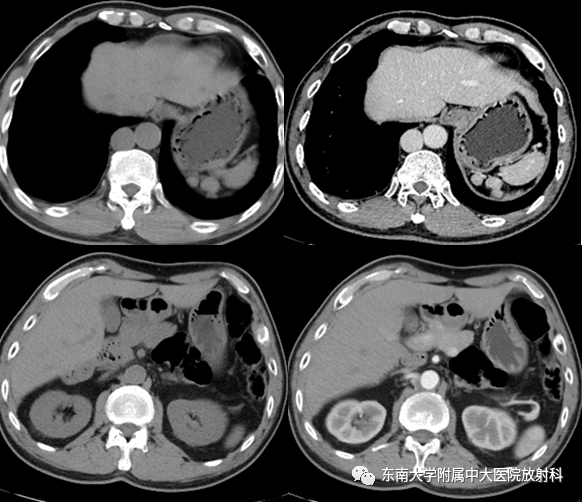

做了ct检查,发现结肠脾曲有一个占位,导致肠管梗阻,大便无法通过,初步